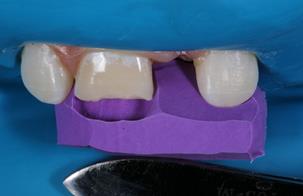

espátula de inserção e pincel, foi realizada a restauração da área correspondente à dentina com RC Vittra APS Unique (FGM Dental Group, Joinville-SC, Brasil) com caracterização do volume e anatomia (sulcos de desenvolvimento) desse substrato (Figura 4). A RC também foi inserida sobre o ângulo cavo superficial para mascarar a linha de transição entre dente e área restaurada até completar toda face vestibular. Todos os incrementos de RC foram fotopolimerizados por 40 segundos; e 13) Acabamento imediato da

Figura 4 Condição clínica após restauração da área correspondente à dentina e caracterização dos sulcos de desenvolvimento.